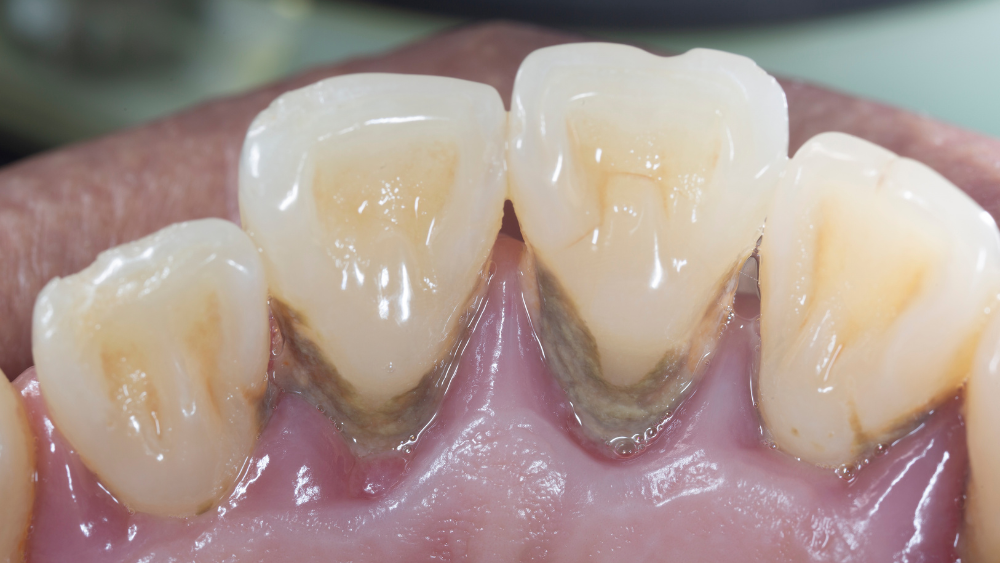

ステージ3:重度歯周炎

重度の歯周病になると、歯周ポケットが6mm以上になり、歯槽骨の破壊が大きく進行します。

歯がぐらついたり、歯ぐきが大きく後退して歯根が露出したりする症状が現れることがあります。

口臭も非常に強くなり、膿が出ることで独特の臭いが発生するケースもあります。